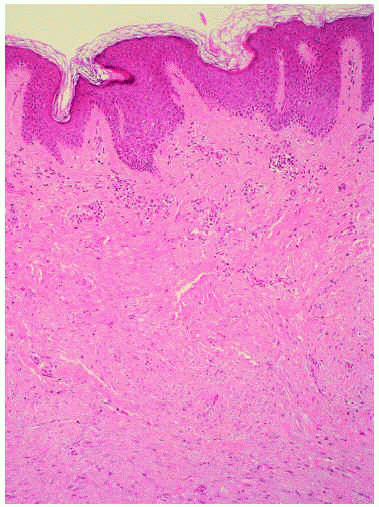

El estudio histológico de tres de estas lesiones mostró en las tres el mismo patrón consistente en una epidermis hiperplásica y una proliferación homogénea de células fusiformes en la dermis profunda que formaba pequeños fascículos con tendencia a disponerse de forma paralela a la superficie cutánea (fig. 4). A gran aumento las células mostraban un citoplasma eosinófilo y núcleos elongados (fig. 5). No se evidenciaban atipias ni mitosis, ni tampoco infiltración profunda del tejido celular subcutáneo.

Fig. 4.--Epidermis hiperplásica y proliferación de células fusiformes paralelas a la superficie cutánea en la dermis reticular con la presencia de anejos en su interior. (Hematoxilina-eosina, x10.)